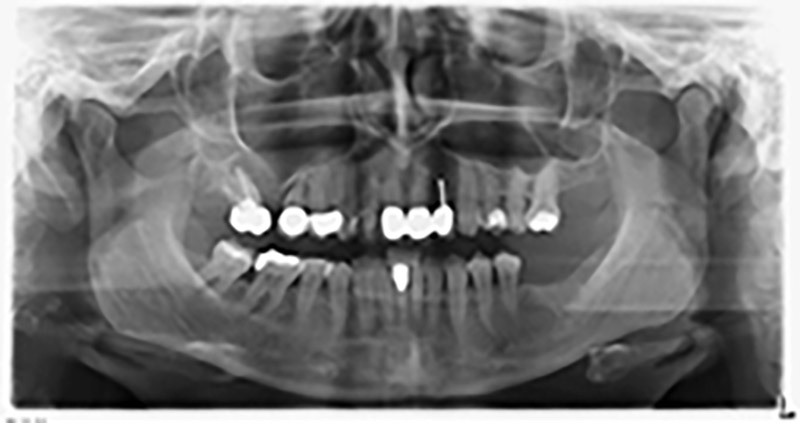

About six months after teeth 16 and 14 were extracted, a digital volume tomography (DVT, Planmeca) examination was performed for planning and risk minimization purposes. It clearly showed that the bone had not regenerated to the desired volume (Fig. 2 to 7).

A sinus floor elevation is required in both region 16 and region 14 to guarantee a fixed restoration based on at least two implants. Relatively large-scale bone augmentation is required due to the residual bone volume being extremely low in this case. Major bone augmentation procedures are invasive and linked to higher patient morbidity, as well as being time-consuming and expensive. It is more difficult to predict the results of the treatment and the risk of failure is increased. The patient was informed of the increased risk and was offered a removable solution, which she consistently rejected.

To restrict the augmentation to region 14, and in consultation with the patient, it was planned that implant 16 would be placed, inclined, in the dorso-cranial direction (Fig. 8).